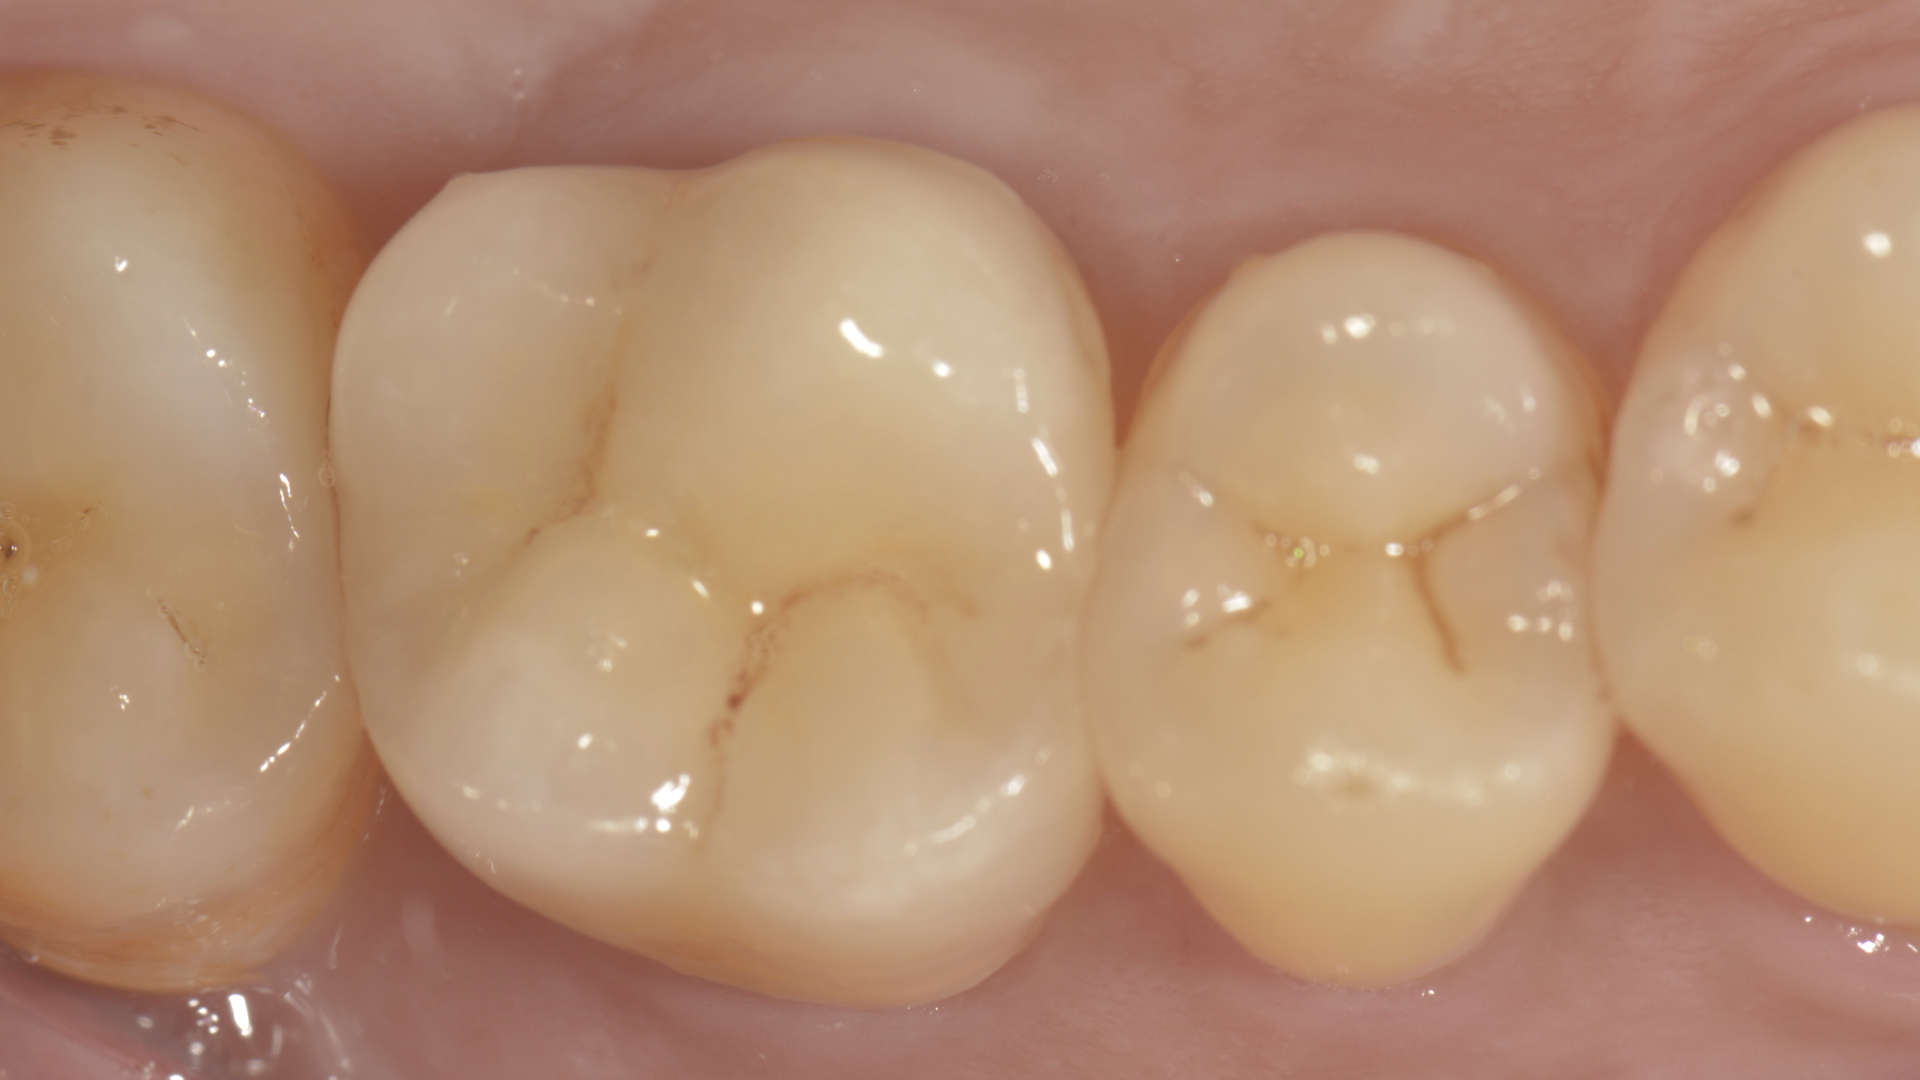

裂痕登發現牙齒有裂痕

牙齒裂開後他院樹脂填補